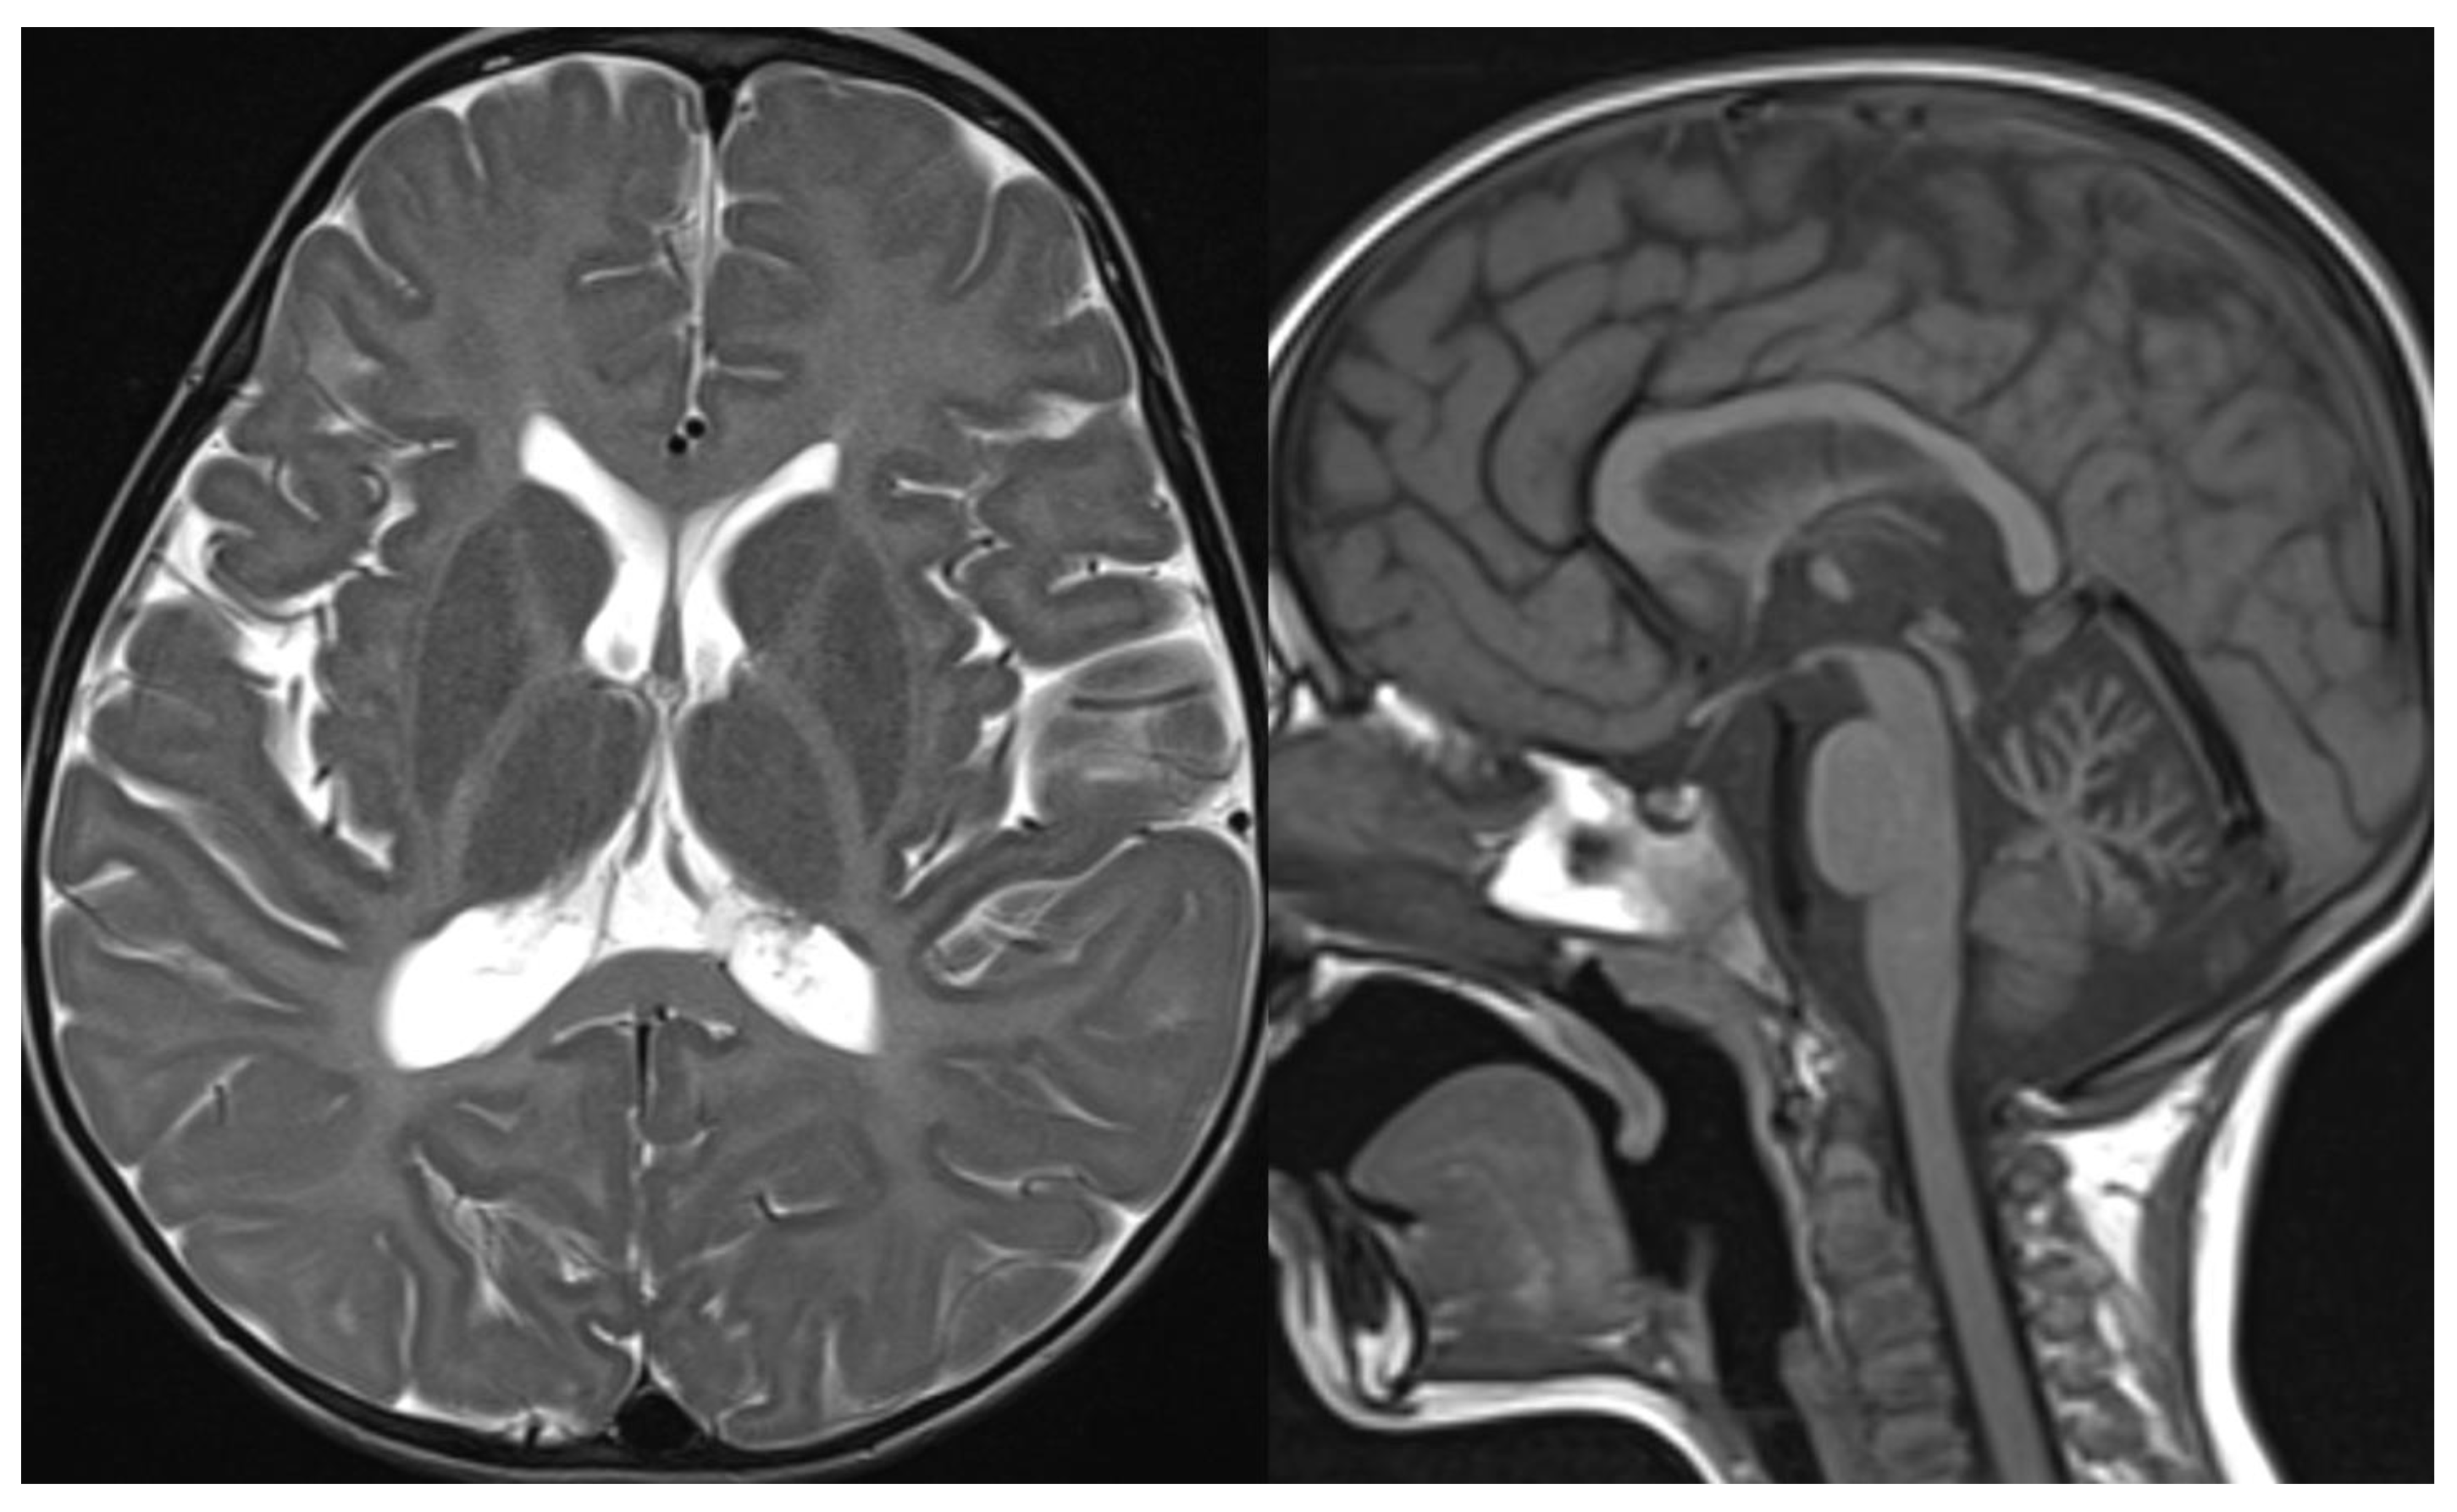

Radiological imaging is limited to MRI since CT and studies with x-rays can increase the risk of genetic mutation in these patients highly sensitive to DNA damage by ionizing radiation [37,38]. MR images reveal diffuse cerebellar atrophy, with initial involvement of the superior vermis and lateral cerebellar hemispheres and unusual decreased cortical thickness along cerebellar hemispheres. Supratentorial brain shows no sign of volume loss. At the same time, confluent hyperintensities in T2/FLAIR and multiple focal hypointensities (thought to be deposits of haemosiderin related to capillary telangiectasia) are seen in deep white matter, mainly in adult patients [39]. Hypoplasia of the inferior vermis and a large cisterna magna were also frequent signs [40] (Figure 7).

Figure 7.

Ataxia telangiectasia (AT). Brain MRI scan of a 10-year-old girl. MR images reveal severe atrophy of the cerebellar hemispheres, decreased thickness of the cortex of superior cerebellar hemispheres, and hypoplasia of inferior vermis.